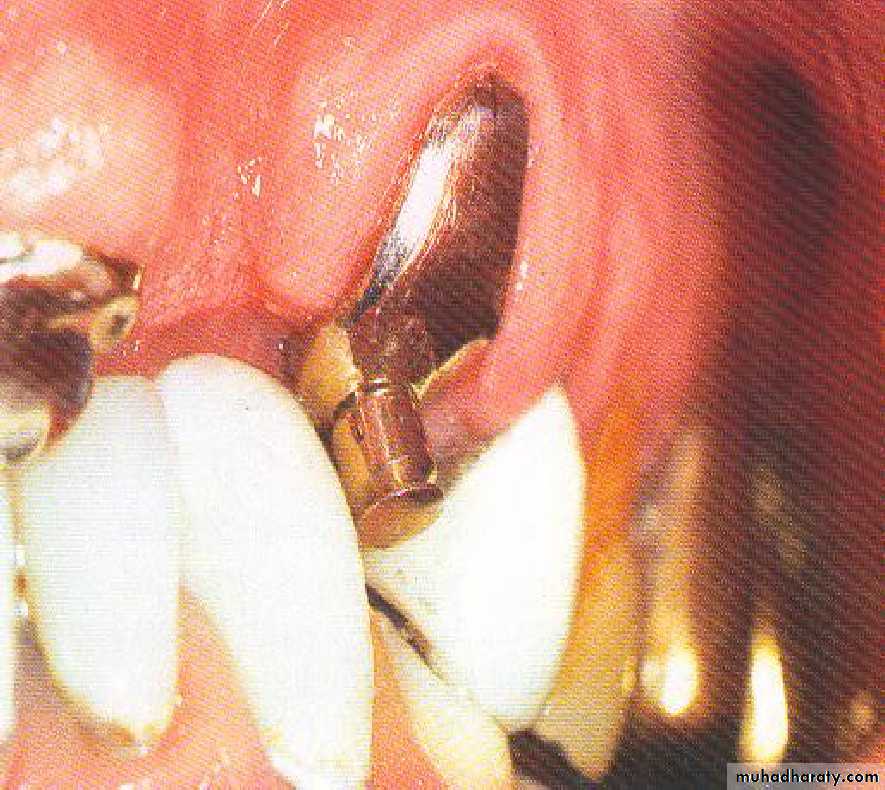

• Endodontic therapy and amalgam plug.

• Endodontic therapy with post and coping.

• .Endodontic therapy and amalgam plug

• .Endodontic therapy with post and cast coping• 5- Endodontic therapy with cast

• May be with or without amalgam plug.

• 5) Submerged root:

• Abutment reduced to level below gingival margin, so need extra retentive attachment (intracoronally).• RCF .... if needed